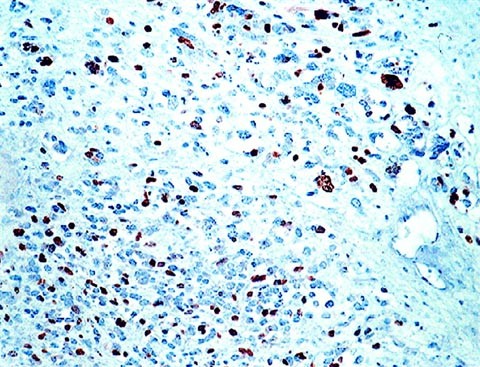

The results of staining for myogenin are summarized in Table 1. Nuclear staining for myogenin was seen in all 48 ARMS (Fig. 1, 2, 3), 20 ERMS (Fig. 4), as well as in the spindle cell RMS. The results of grading in the RMS cases are summarized in Table 2. Grade 4+ staining with 75 to 100% of nuclei staining positive was present in 44 ARMS, two cases showed 3+ staining and in another two cases only 20% of nuclei stained, consistent with 1+ staining. In contrast, in the ERMS group, 17 of 20 cases showed 1+ staining, with the number of positive staining nuclei ranging from rare positive to 25%. In three ERMS, staining was graded as 2+, with 25 to 50% nuclei positive. None of the ERMS showed Grade 3+ or 4+ staining. The single case classified as spindle cell RMS showed 3+ staining. In 66 of the 69 RMS, desmin-stained slides were available for review and all cases stained desmin-positive. In some of the more primitive appearing ARMS, however, the number of myogenin-positive cells clearly exceeded the desmin positivity (Fig. 5).

Myogenin-positive cells were identified in the two ectomesenchymomas, correlating with the desmin positive areas. In one case, the majority of the tumor was composed of undifferentiated cells that expressed only mic-2, whereas, in focal areas, the mic-2 positive cells also co-expressed myogenin, desmin and actin, as illustrated in Figure 6, A-C. Staining for myogenin (as well as desmin) was also noted in two of six nephroblastomas, and correlated with areas of myogenous differentiation (not shown). Staining for myogenin was absent in all other tumors studied (Table 1). Among the normal tissues evaluated for myogenin, positive staining was seen only in fetal striated muscle, as expected. All other tissues (adult and fetal) were negative.

Interestingly, we observed distinct myogenin positivity in the two ectomesenchymomas included in our study, consistent with true rhabdomyoblastic differentiation. The distribution of myogenin-positive cells correlated with areas of desmin positivity (as seen in Fig. 6), although, in one case, myogenin-expressing cells were more numerous than those positive for desmin. Although Northern blot analysis has demonstrated myogenin transcripts in three of five cell lines derived from these biphenotypic tumors in a prior study (17), other studies evaluating myogenin expression have not included examples of this rare tumor. Because these tumors can be composed almost entirely of undifferentiated primitive appearing cells that may stain for mic-2 (as in the case illustrated in Fig. 6), myogenin expression can be very helpful in distinguishing these from ESFT. Additionally, two Wilms' tumors with focal myogenous differentiation marked positively with both myogenin and desmin, confirming rhabdomyoblastic differentiation in these tumors, similar to a case previously reported by Wang et al. (3).